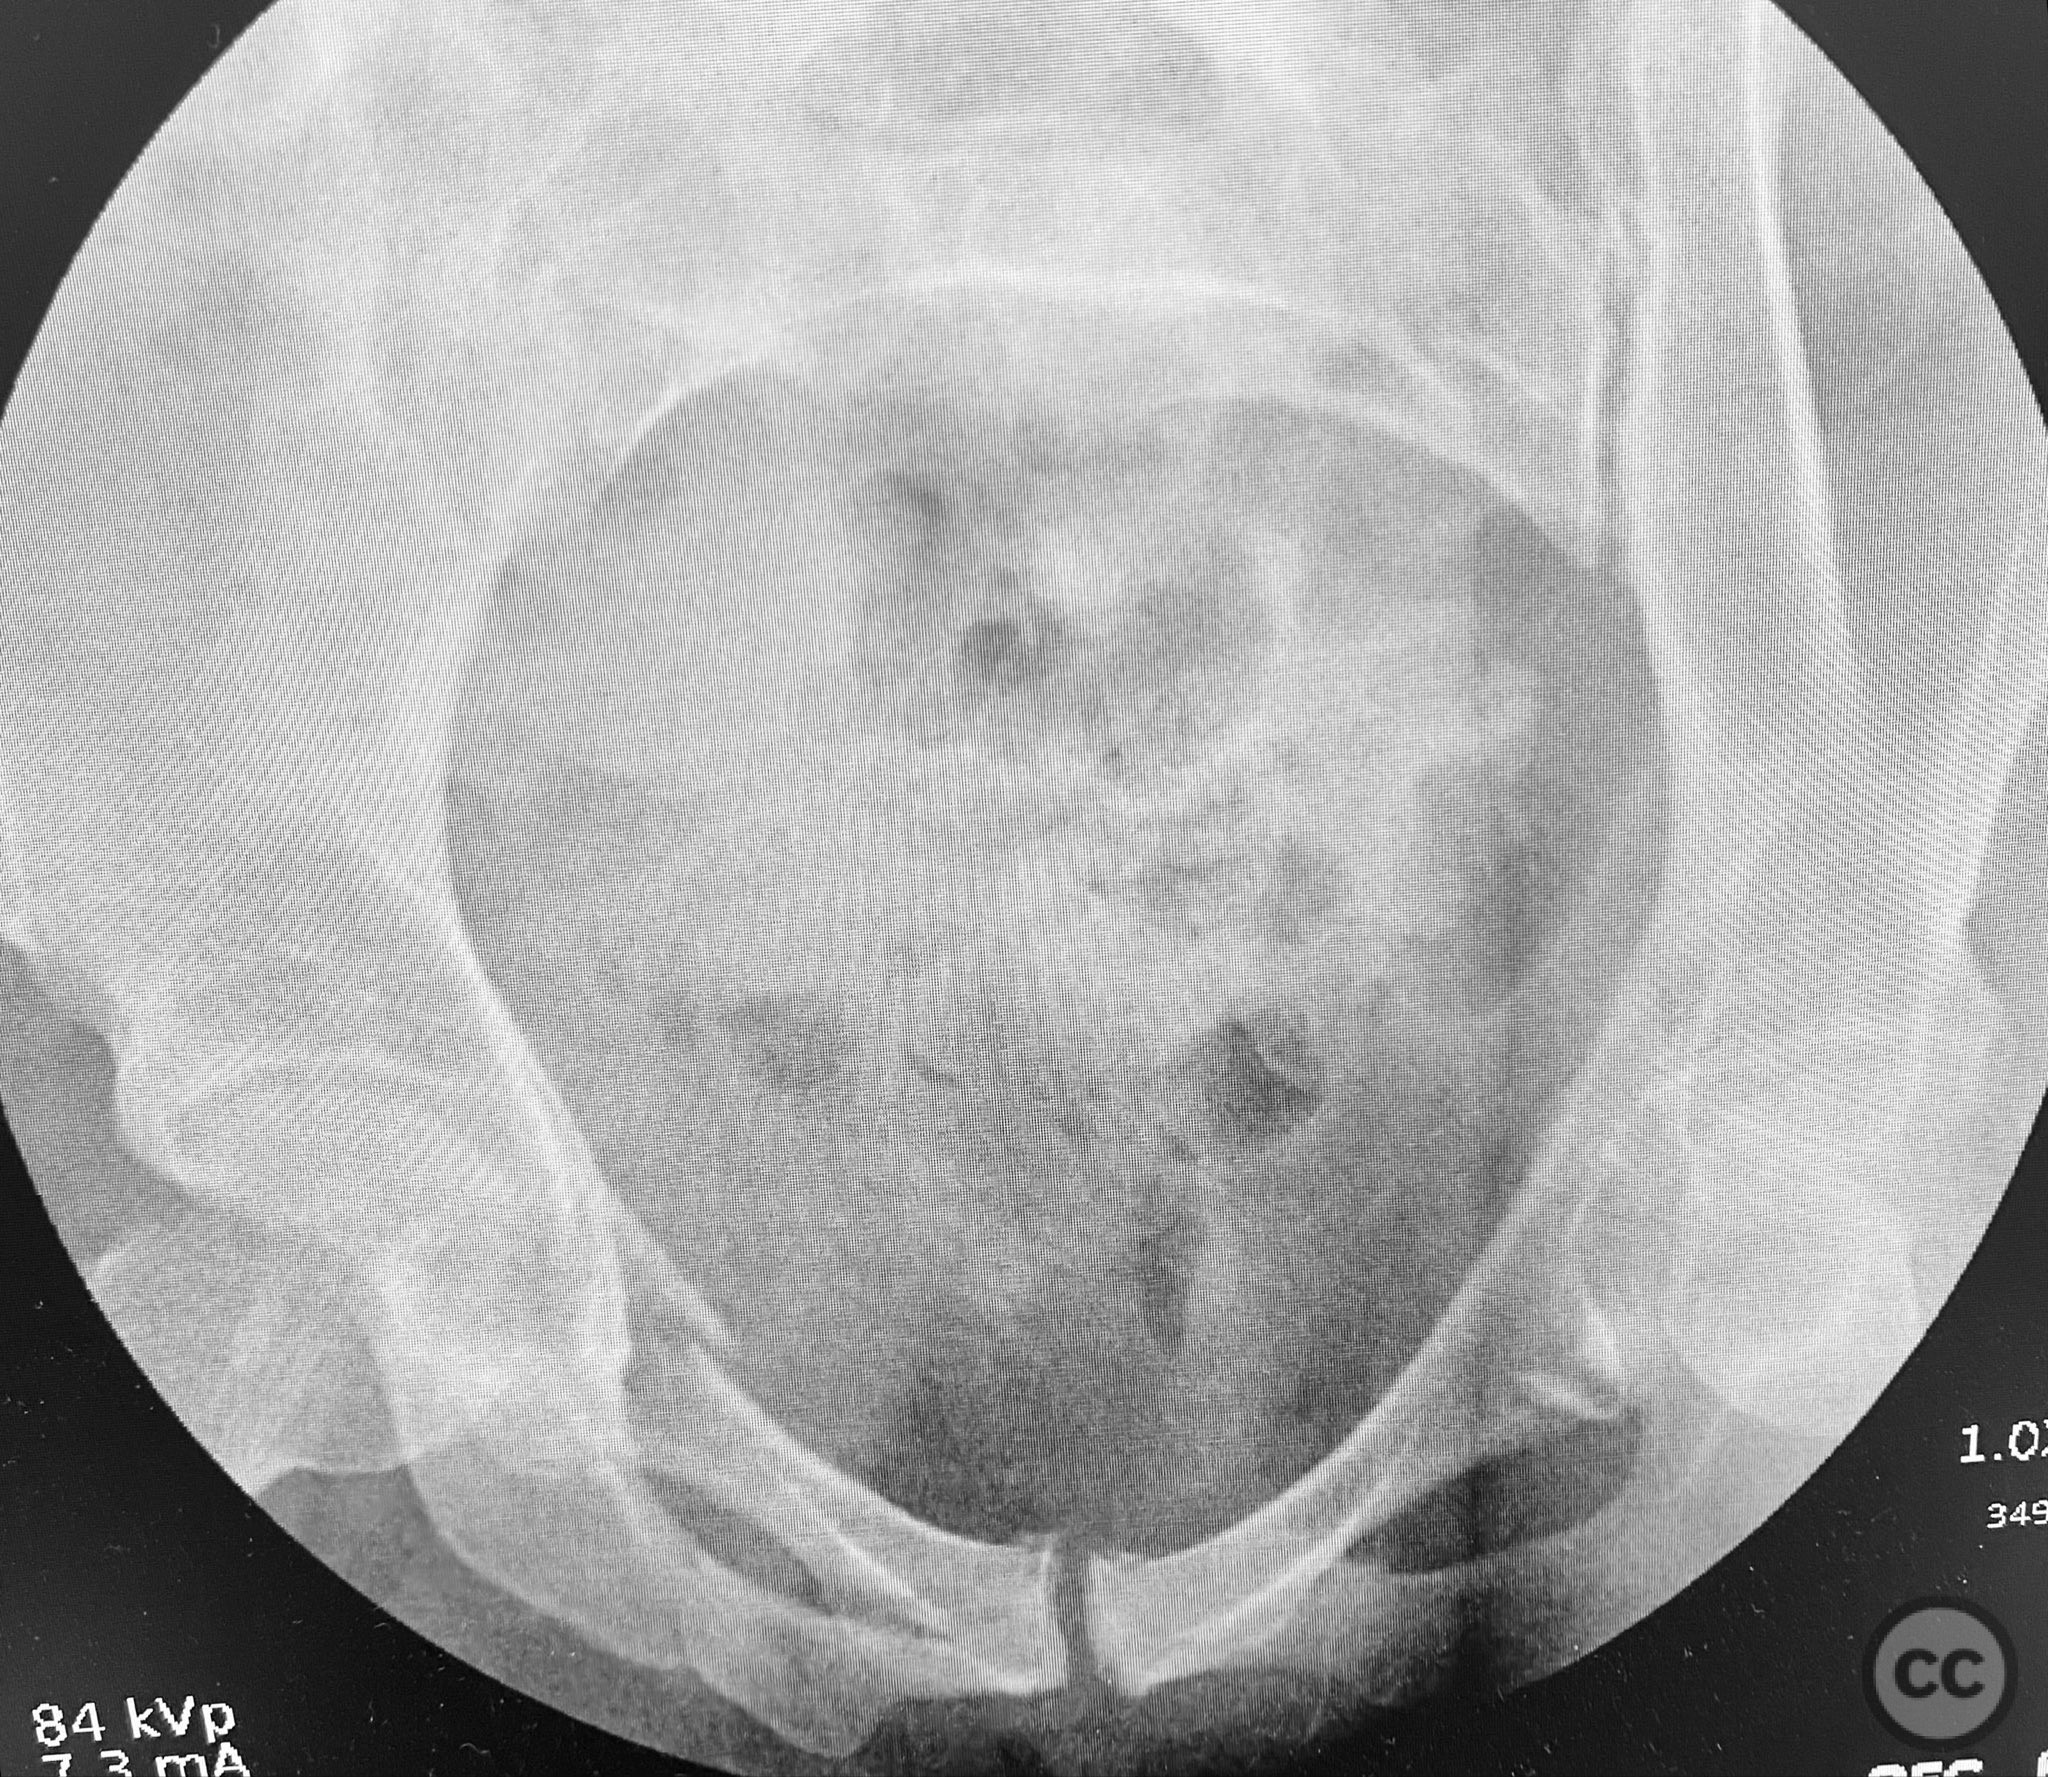

Clinical and radiological findings:  A middle-aged patient involved in a motor vehicle collision presented initially with a closed ankle fracture-dislocation and minimal pelvic complaints. Following closed reduction and splinting of the ankle, the patient developed severe pelvic pain (9/10) with any attempted movement. Neurological and vascular examination was not specified. Computed tomography demonstrated minimally displaced fractures of the posterior ilium, sacral ala, and bilateral pubic rami. AP CT surface renderings revealed subtle but clinically significant displacement and deformity of the pelvic ring, which was difficult to appreciate on standard axial images.

Planning remarks:  The preoperative plan was to assess pelvic stability under anesthesia, utilizing manual compression of the cristae iliacae with intraoperative fluoroscopic inlet imaging to identify sites of instability. Percutaneous screw fixation was planned for unstable zones, with reduction refined as necessary under imaging guidance.